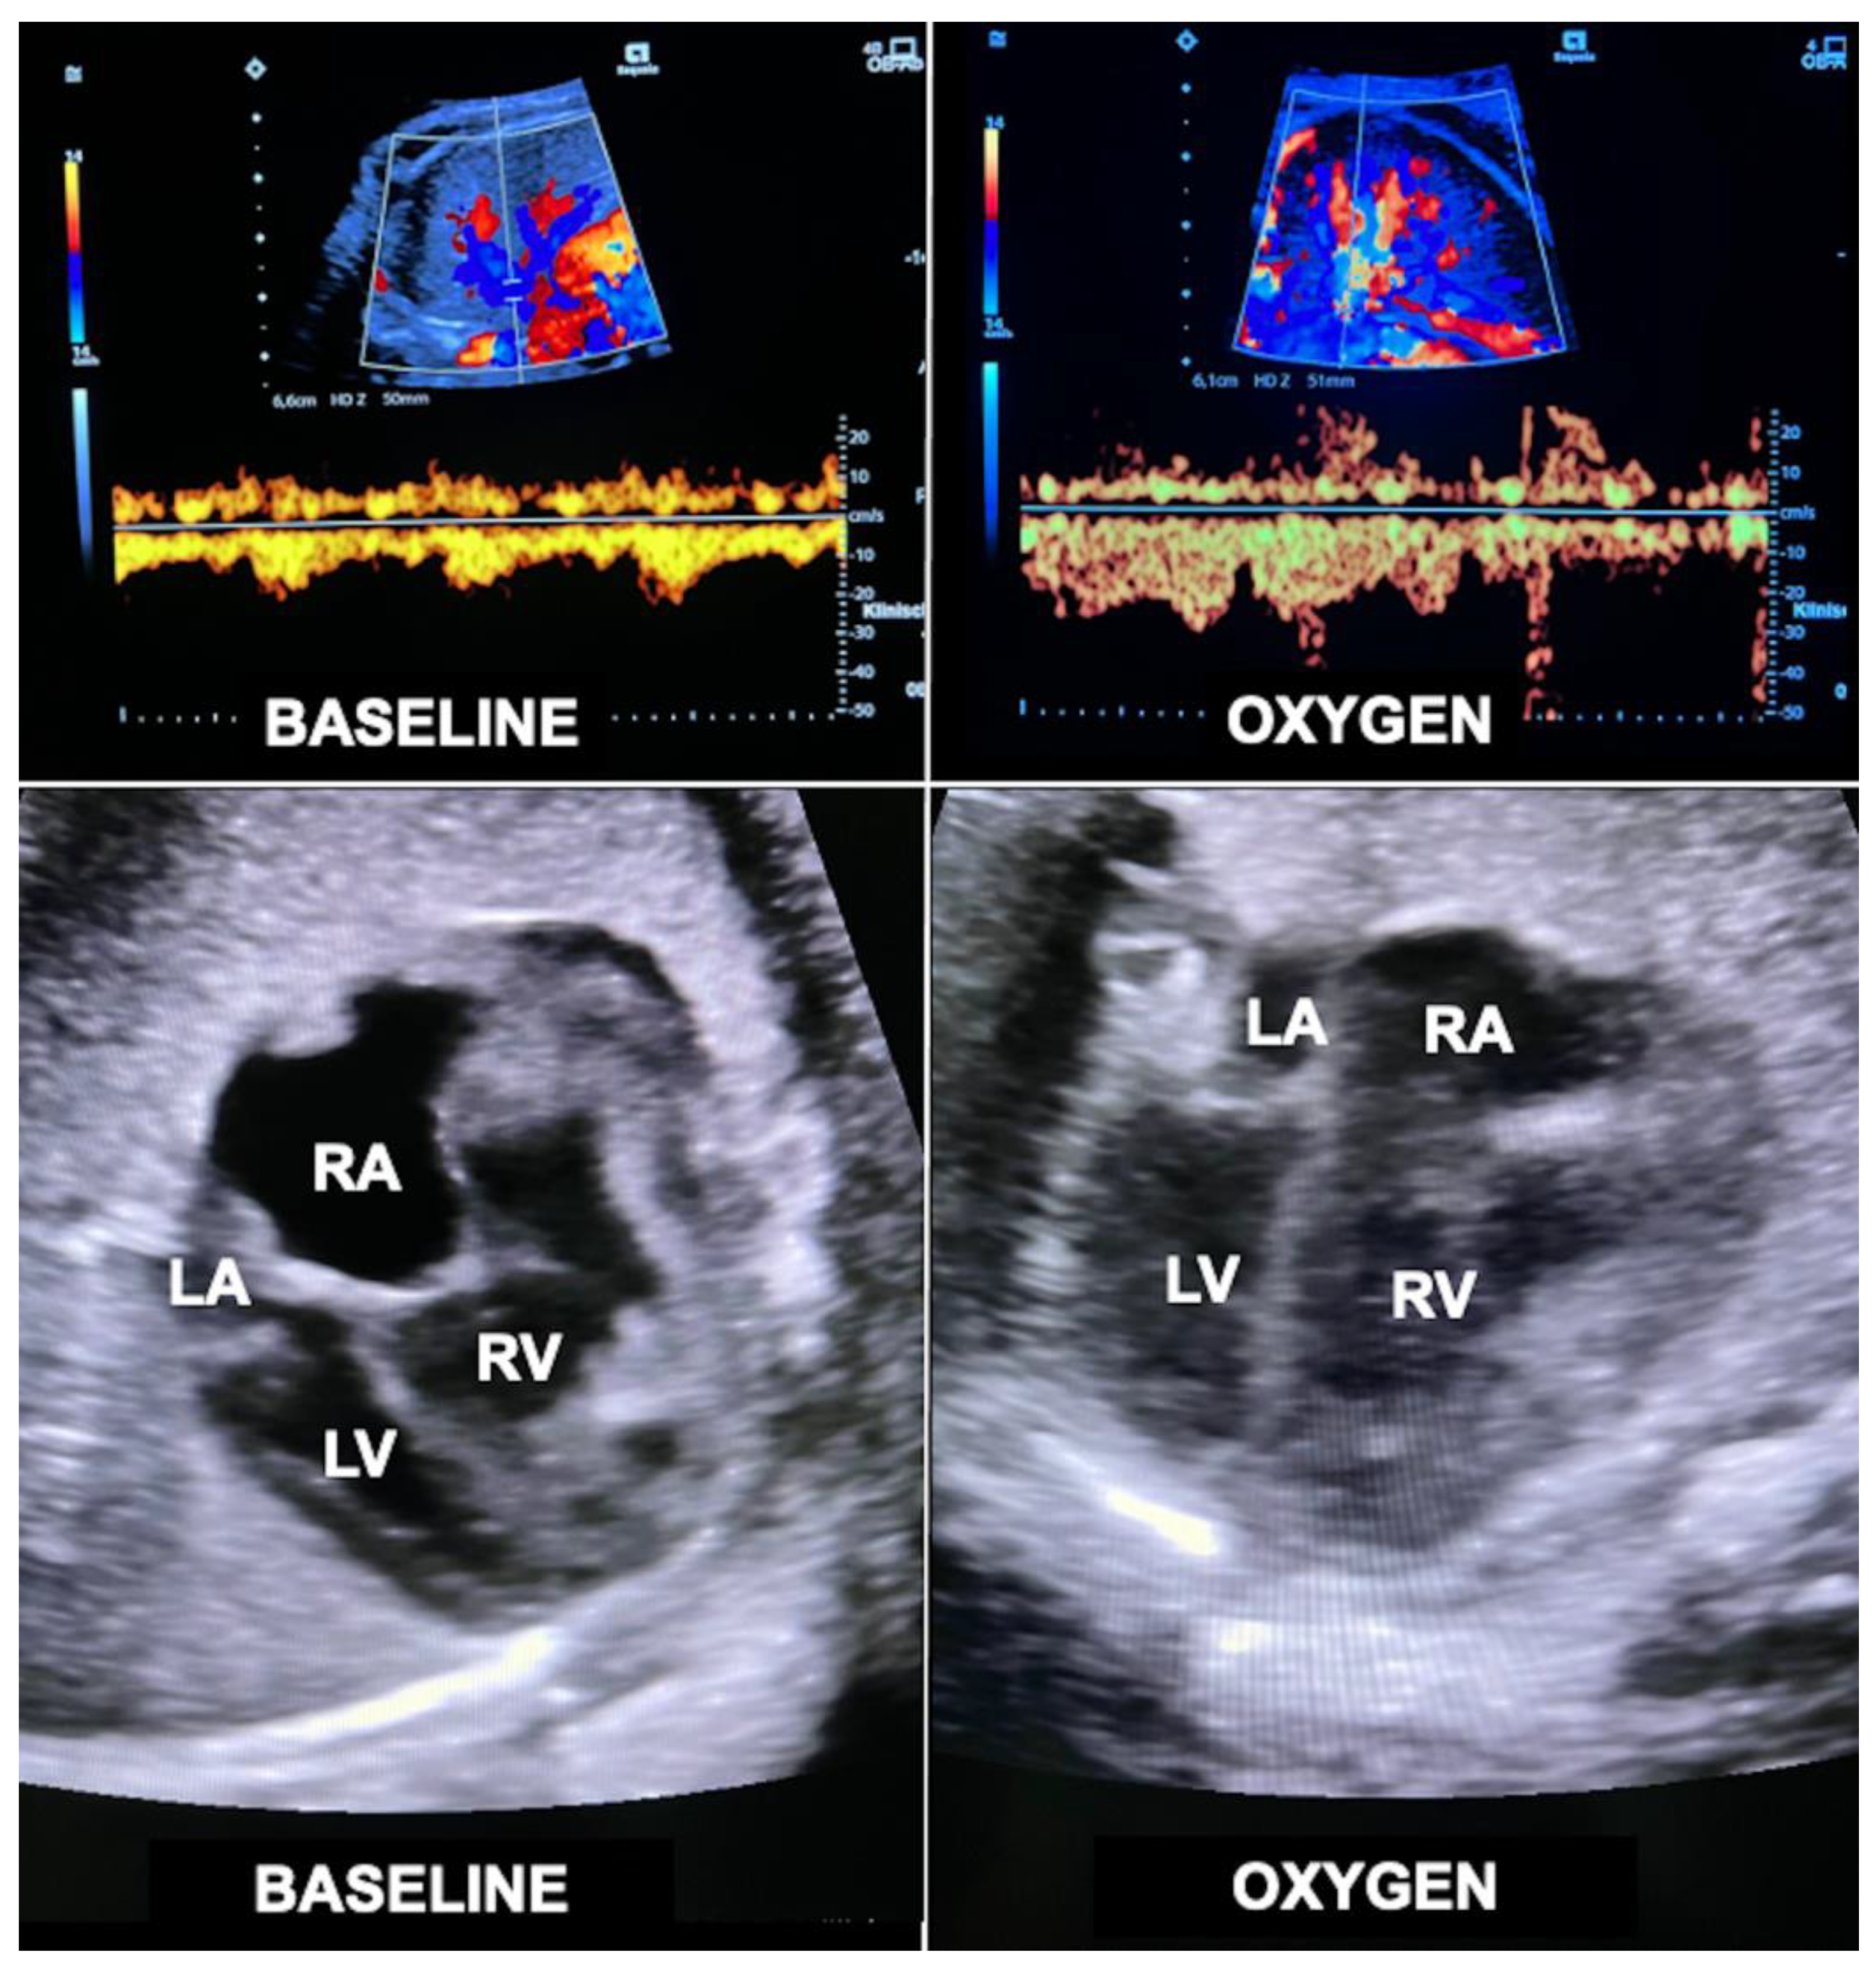

The principle is simple: A small fraction of supplemental oxygen being inhaled by pregnant women beyond 30 weeks of gestation crosses the placenta and increases the oxygen content of the fetal blood, thus inducing fetal pulmonary vasodilatation and a marked increase in lung blood flow (Figure 11). Through this mechanism, the preload from the increased pulmonary venous return challenges both hypoplastic left and right heart structures (Figure 11). Through providing 6 L/min of O2 via a face mask to the mother (approximately 35–40% oxygen) three times daily (8:00–12:00/14:00–18:00/20:00–23:00; total 10–11 h/day) from 32 + 0 to 34 + 0 weeks of gestation onwards until delivery, impressive degrees of catch-up growth can be observed in suitable cases [103].

Figure 11.

Acute loading effect of materno–fetal hyperoxygenation on the left ventricle in a fetus with hypoplastic left heart complex at 34 + 2 weeks of gestation. Top—color Doppler interrogation of a pulmonary vein before (left) and after 10 min (right) of materno–fetal hyperoxygenation demonstrates a marked increase in pulmonary flow. Bottom left—there is marked disproportion between the hypoplastic left (LV) and the dilated right ventricle (RV) before hyperoxygenation (BASELINE). Bottom right—after only 10 min of materno–fetal hyperoxygenation (OXYGEN), the left ventricle shows substantially improved filling at end diastole. Over several weeks, this effect results in catch-up growth of hypoplastic left heart structures. LA = left atrium; RA = right atrium.

Despite its enormous potential for fetuses with a wide spectrum of cardiovascular malformations, doubts were raised about the efficacy of the approach. It was feared that the increased pulmonary venous return would interfere with the normal right to left shunt across the oval foramen toward the left side of the heart, neutralizing additional loading of the left side of the heart. Whereas such a mechanism may be present in some fetuses, it is not at all applicable to fetuses with an imperforate atrial septum and an otherwise structurally normal heart. This subgroup presents with severe left heart underdevelopment (z-scores ≤ −3) and in my experience benefits particularly well from the volume challenge provided to the left side of the heart by chronic intermittent materno–fetal hyperoxygenation [104].

In other fetuses with fetal left heart hypoplasia, abnormal, preferential streaming of ductus venosus blood toward the right side of the heart can be observed [105]. This flow abnormality not only results in decreased flow across a patent oval foramen but is also associated with lower pulmonary blood flow. Both factors contribute to the development of left heart hypoplasia and may be ameliorated by materno-fetal hyperoxygenation.